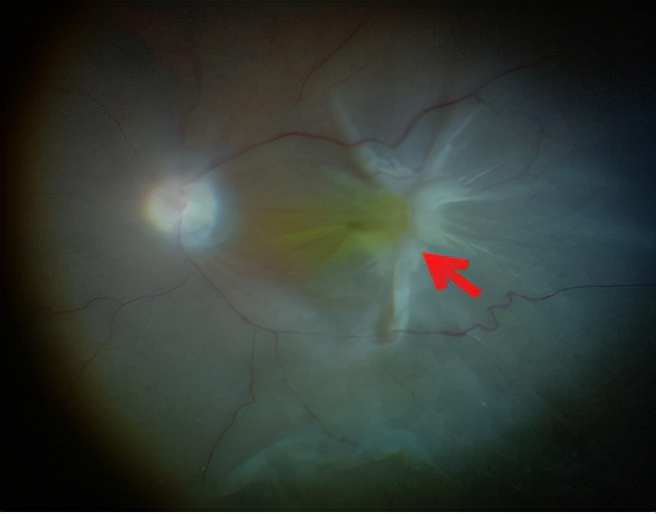

图5. 术中可见视网膜脱离,合并PVR的星状皱褶(箭头处)